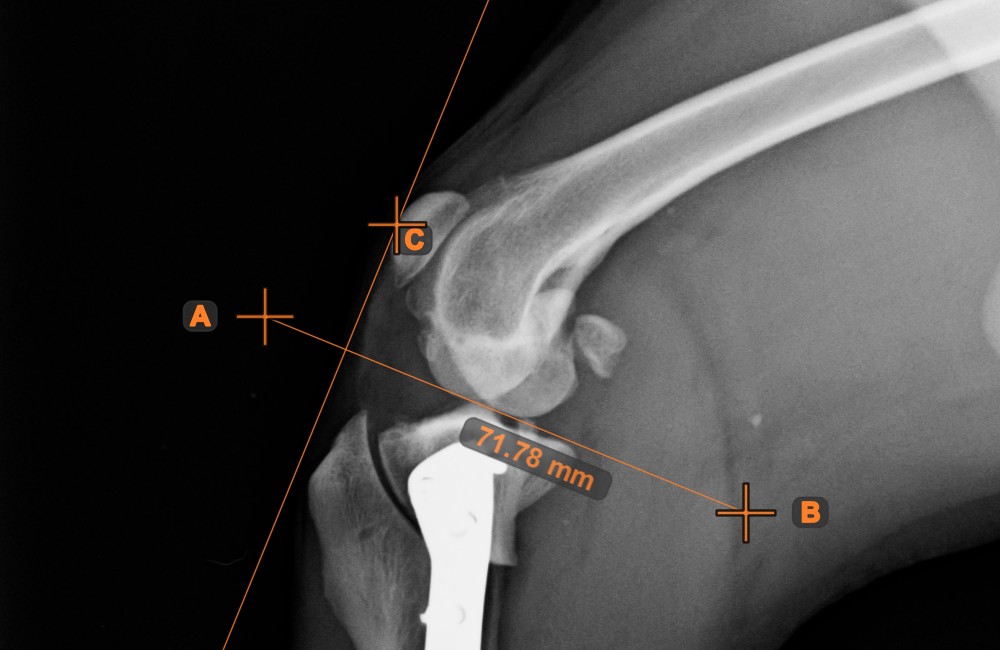

Distance of Line and Point¶

Measure the distance between a line and a specific point on the scene using the Distance of Line and Point

tool.

Select the tool from the left toolbar and assign it to one of the available mouse buttons. Start the measurement by selecting an already existing line from the scene. To complete the measurement, place the desired point on the scene or choose from an already exisiting point. The distance between the line and the point will be automatically calculated.

Modify the measurement by moving any of the points using the Select/Move Item